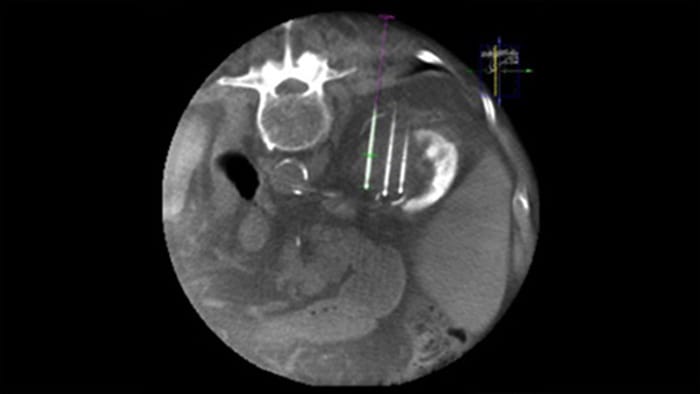

Imágenes de lesiones posteriores a la ablación con la THC

THC image

Adquiera una THC posterior a la ablación para demostrar la extensión de la cobertura del tumor y confirmar la finalización de su tratamiento.